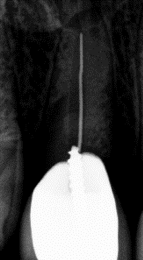

Canals cleaned and shaped to the apex?

The filling should go to the tip of your root. Not filling enough (under-fill) can leave space for harmful bacteria to grow. A filling that goes beyond the root tip (over-fill) can cause damage to the bone, sinus, or even nerve damage in severe cases. Over or under filling increases the chances that you'll need to have another procedure down the road.

Adequate root filling density?

The canals should be filled without leaving any spaces between the walls of the tooth. Spaces can leave room for bacteria and toxins that eventually cause an infection, often requiring another root canal.